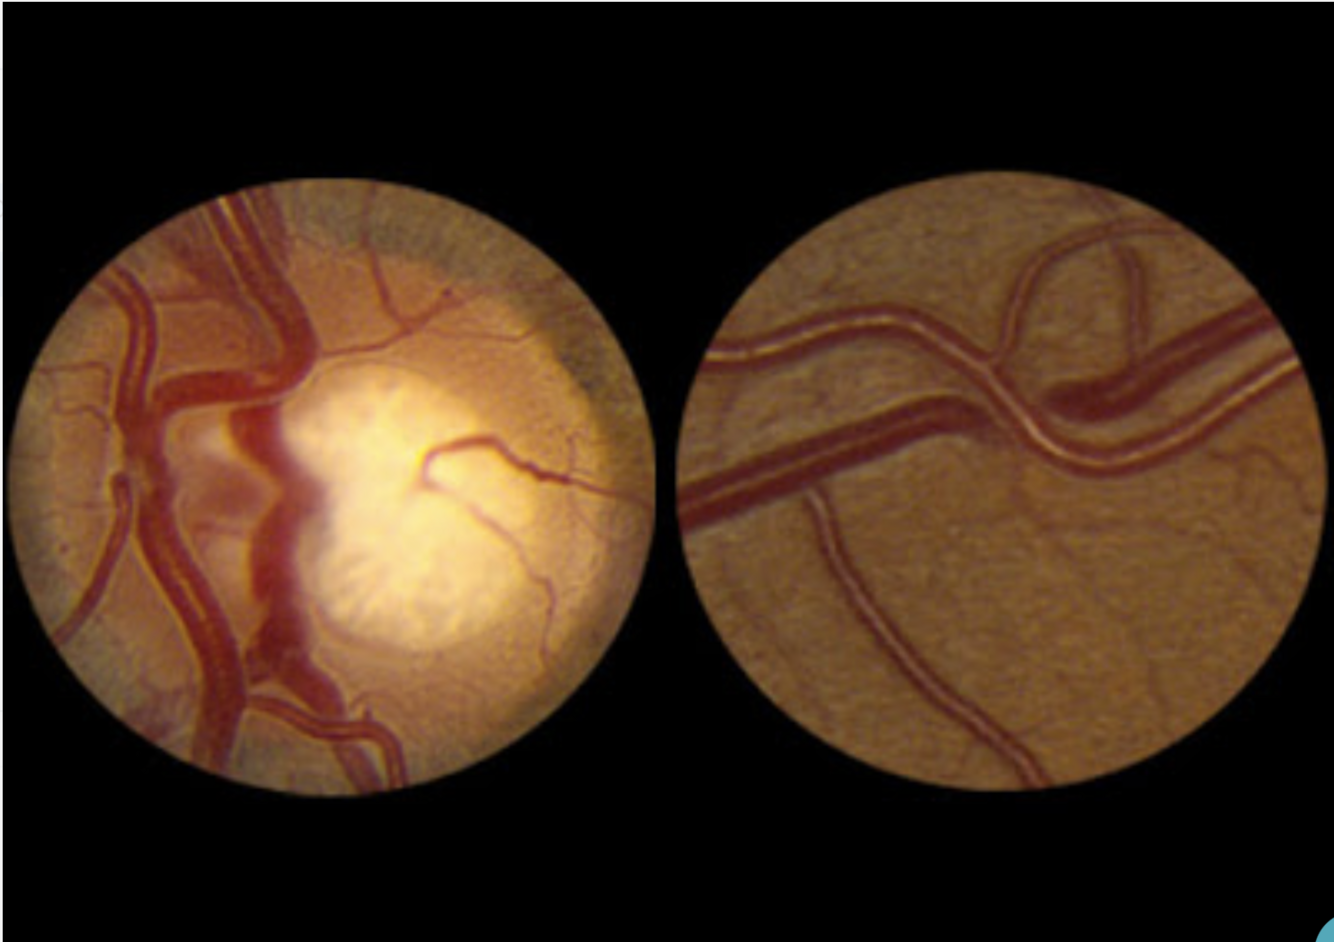

Hipertenso com este achado

O que representa na classificação de KWB?

A

PAPILEDEMA

Grau IV na classificação de Keith-Wagener-Barker